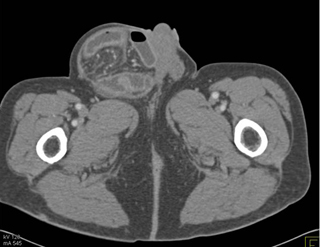

In this patient with symptoms of SBO the best dx is?

inguinal hernia with incarcerated small bowel